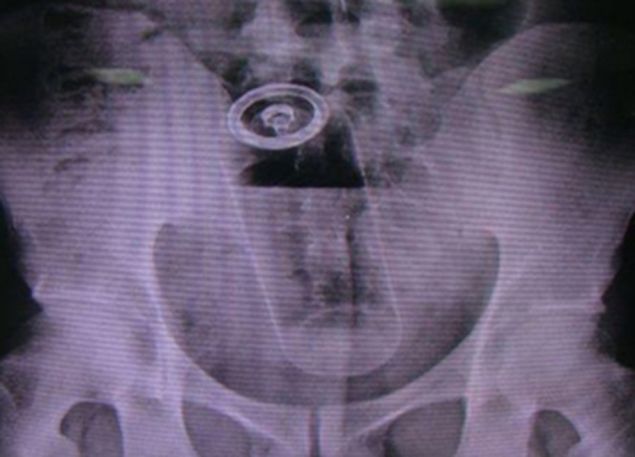

Lista rusinoasa a radiografiilor inedite este completata de imagini cu o vanata, o jucarie de plastic, un deodorant sau chiar un telefon mobil! Toate aflate "captive" in aceeasi zona a corpului.